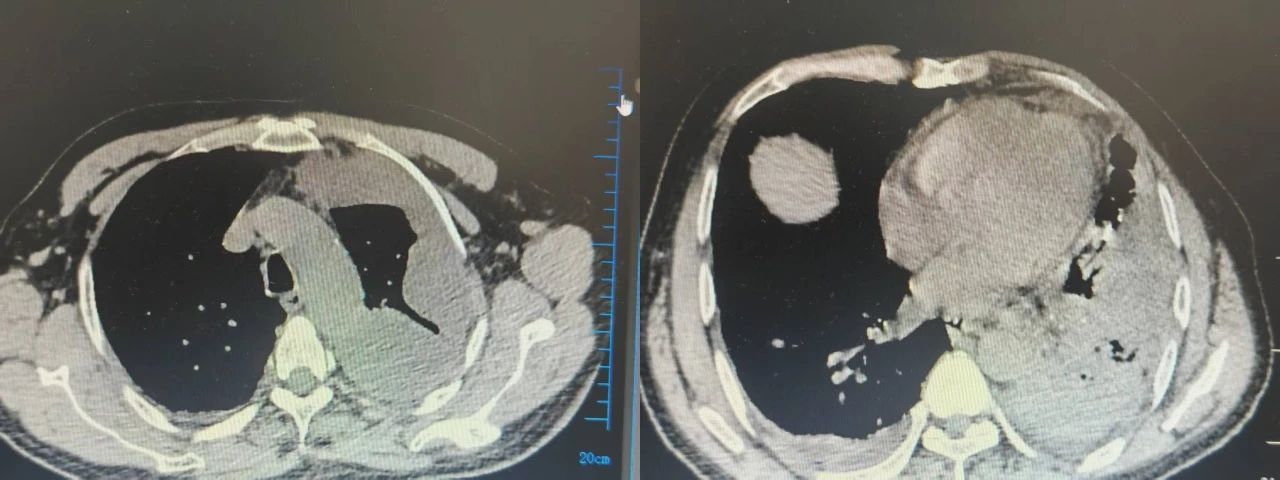

经过3天的积极救治,引流脓液量减少,胸部CT提示:脓腔缩小,血气分析提示:呼吸衰竭明显改善,已脱离吸氧。在医护人员的治疗和精心照料下,患者已脱离危险,目前正在进一步治疗中。